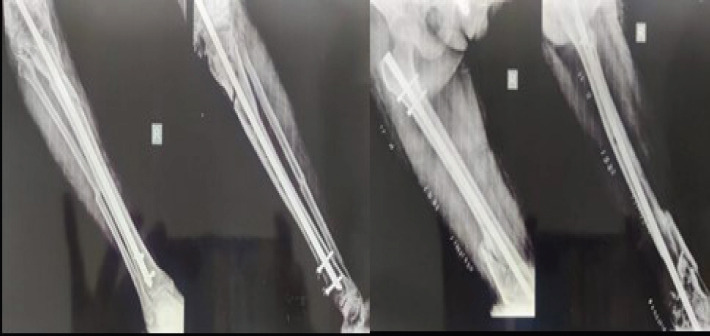

Conclusion: An efficient salvage technique that provides permanent pain relief and functional stability is knee arthrodesis. The need of customized treatment planning in handling complicated fracture situations is highlighted by this example.